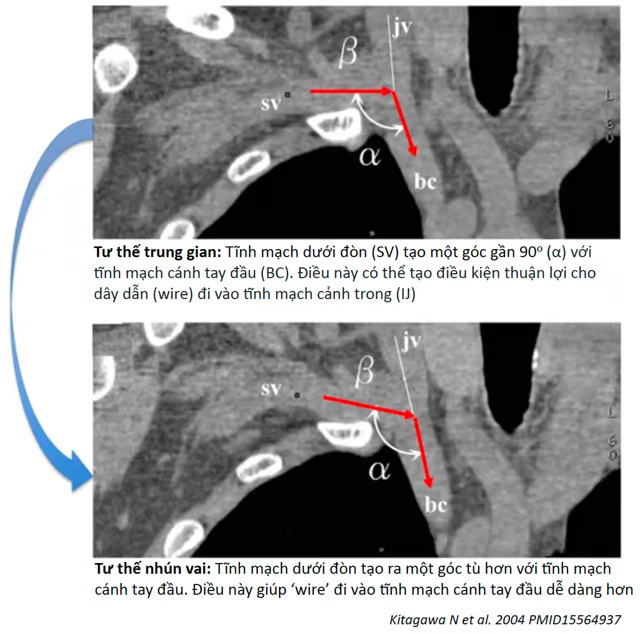

3. Nâng vai lên trên làm tăng góc giữa tĩnh mạch dưới đòn và tĩnh mạch cánh tay đầu (như hình dưới). Điều này giúp việc luồn dây dẫn và catheter đi xuống tĩnh mạch cánh tay đầu dễ dàng hơn (thay vì đi theo hướng không mong muốn lên tĩnh mạch cảnh trong).